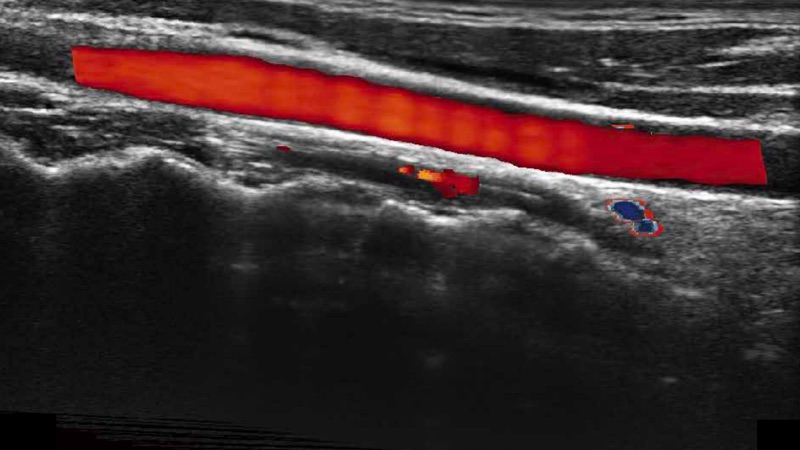

高分辨率血流成像技術(shù)提高了對(duì)低速血流信號(hào)的檢測(cè)能力。在提高空間分辨率的同時(shí),也克服了血流外溢現(xiàn)象,為用戶(hù)提供更加真實(shí)的血流動(dòng)力學(xué)信息。

通過(guò)色彩血流和實(shí)時(shí)寬景相結(jié)合,可觀察到完整的靜脈或動(dòng)脈的血流,方便醫(yī)生檢查。實(shí)時(shí)掃查過(guò)程中,如有任何操作失誤也可以很容易地進(jìn)行回掃擦除,而不會(huì)中斷掃查。